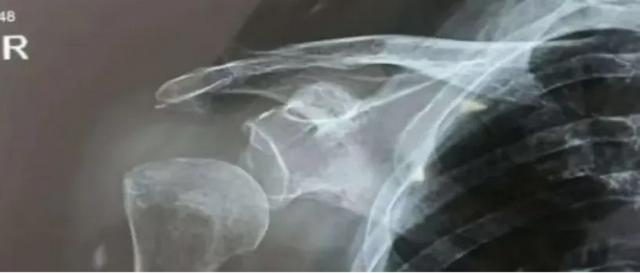

您或您的身边是否有人出现过这种情况(如下图),是否因此而惊慌、失眠、不知所措。不要担心,这是中风后肩关节半脱位,介入康复能帮大忙。下面,湖南省直中医医院针灸康复治疗中心专家就来为您介绍肩关节半脱位的康复治疗方法。

肩关节半脱位又称不整齐肩,在偏瘫患者中发病率为60%—73%,是十分常见的并发症,表现为肱骨头在关节盂下滑,肩峰于肱骨头之间出现明显的凹陷,视觉上表现出手臂“掉下来”的状态。

3、配合影像学

如X线片,CT、肌骨超声等,可确定损伤程度和范围,发现潜在风险。